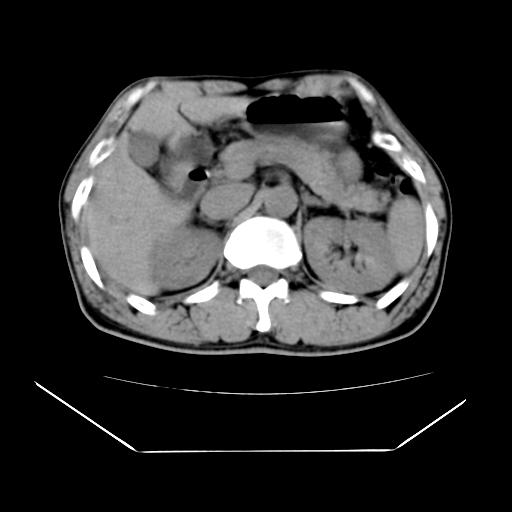

男性,55岁,外院体检afp明显升高,但b超未发现异常,否认乙肝病史。来我院ct增强。有延时扫描。

延时扫描完全充填,血管瘤

肝脏右叶动脉期可见低密度影,至延迟期被充填,考虑血管瘤可能性大。

肝右叶病灶

不排除肝右叶肝癌可能。

肝6段血管瘤

血管瘤可能性大。

考虑肝右静脉影。